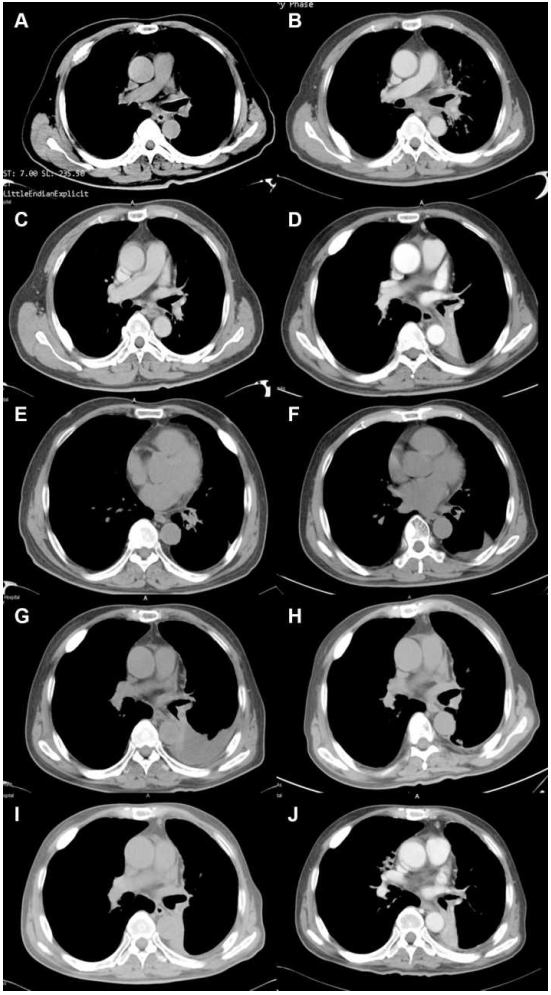

图2.(A)2013年1月诊断时的基线CT扫描。(B)2014年8月化疗后的PD。(C)2015年2月伊可替尼治疗后的PR。(D)2015年12月伊可替尼治疗后的PD。(E)2016年9月奥西莫替尼治疗后的PR。(F)2017年12月奥西莫替尼治疗后的PD。(G)2018年4月化疗后的PD。(H)2018年11月,阿法他尼和阿帕替尼联合治疗后的PR。(I)2019年2月,阿法他尼和阿帕替尼联合治疗后的PD。(J)2019年7月,白蛋白结合紫杉醇和托瑞帕利单抗治疗后的PR

患者最初接受培美曲塞和顺铂一线化疗,紫杉醇脂质体(紫杉醇的一种剂型,不同于nab紫杉醇)和卡铂二线化疗。患者总共获得了16个月的无进展生存期。2014年8月,患者出现进展性疾病(PD)(图2B)。患者在进展过程中没有任何组织或液体活检,对原发性肺组织进行了EGFR检测,结果显示EGFR外显子19缺失。

随后,患者在2014年10月接受了伊可替尼作为第三线治疗。伊可替尼是一种EGFR-TKI,已于2011年被国家医药管理局(NMPA)批准用于治疗EGFR突变型NSCLC。根据实体瘤1.1(RECIST 1.1)的疗效评价标准,伊可替尼获得部分疗效(PR),PFS为13.5个月(图2C,2D)。然后,患者转为吉西他滨和奈达铂的4个周期治疗,并实现了PFS 7.5个月。

2016年8月1日,疾病再次进展,基因检测显示EGFR T790M呈阳性。患者随后接受了奥西替尼治疗。1个月后,患者达到PR(图2E,2F),持续了16个月。进展后,患者改用长春瑞滨联合洛铂治疗,2.5个月后出现PD(图2G)。

随后,对患者的血浆和活检组织样本进行基于捕获的靶向测序,在血浆和组织样本中显示EGFR 19 del和EGFR T790M。此外,仅从血浆中检测到EGFR T790M-cis、EGFR C797S,而仅在组织样品中观察到拷贝数为3.5的HER2(ERBB2)扩增。2018年4月,患者接受阿法替尼联合阿帕替尼治疗,获得PR(图2H),PFS超过10个月。

2019年2月,患者出现左叶肿块增大的PD(图2I)。再次行纤维支气管镜活检及分子检测。结果显示在肿瘤组织中有EGFR 19del和T790M,无HER2扩增,在血浆中有EGFR 19del-T790M-cis-C797S。2019年4月1日,治疗方案改为白蛋白结合紫杉醇和PD1抑制剂托瑞帕利单抗4个周期。在治疗过程中,患者没有出现严重的不良反应。经过2.5个月的治疗,患者达到PR(图2J)。然而,由于经济困难,治疗被终止。患者于2019年9月去世,总生存期为80个月。